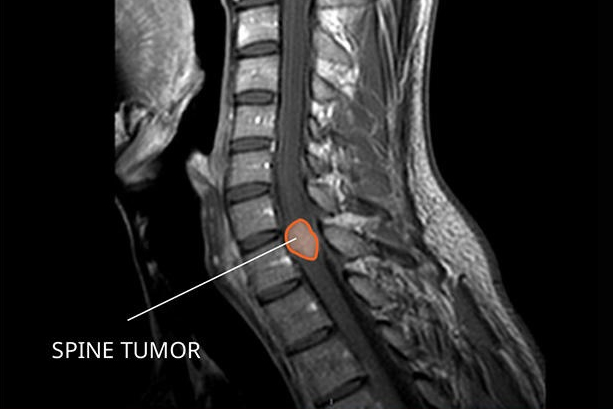

SRF TAKES PRIDE IN PRESENTING TO YOU A FEW INTERESTING CASES

More than 300 Underprivileged Patients have been Operated through our Foundation over the last 15 years !

book_4 Notable

Cases